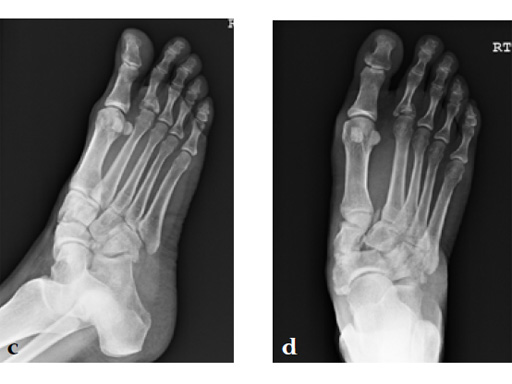

A 48-year-old woman, with hallus valgus and hypermobile medial column, also resulting in pes plano abductovalgus (flatfoot).

Surgery consisted of first TMT and intertarsal corrective osteotomy plus fusion with movement of the first MT lateral and plantar. This corrects the hallus valgus as well as the PPAV (and stabilizes the medial column).

A 60-year-old woman with pes plano abductovalgus (flatfoot deformity).

The patient was treated by headless compression screw 6.5 tuber osteotomy, TMT plantarflexing osteotomy, and first TMT fusion a plate.